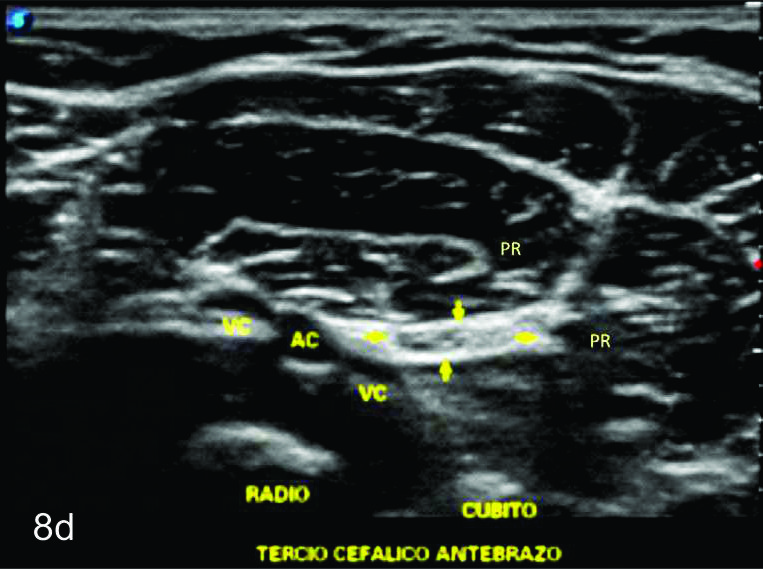

Figura 8

Nervio mediano

Serie de cortes axiales del nervio mediano desde su origen a nivel del hueco axilar hasta el sector distal del antebrazo previo a su ingreso al túnel del carpo. Se identifica el mismo señalado por flechas amarillas y con la palabra mediano. AA-arteria axilar, VA- vena axilar, AH- arteria humeral, VH- vena humeral, VB- vena basilar, AC- ateria cubital, VC- vena cubital, BA- músculo braquial anterior, PR- músculo pronador cuadrado, FS- músculo flexos superficial, FP- músculo flexor profundo, PC- músculo pronador cuadrado. A- axila, se identifica el nervio superfical a la arteria axilar, B- tercio medio del brazo en canal bicipital medial, lateral a la arteria humeral, C- codo, medial al tendón distal del bíceps braquial y a la arteria humeral luego de cruzarla, superficial al músculo braquial anterior, D-antebrazo sector cefálico, entre las dos cabezas del pronador redondo, E- tercio medio del antebrazo, entre los músculos flexor superficial y profundo F- tercio distal antebrazo, superficial al pronador cuadrado.